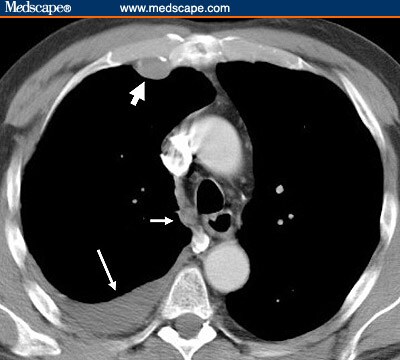

Mesothelioma img.Medscape. Malignant pleural mesothelioma. Malignant pleural mesothelioma usually begins as discrete plaques and nodules that coalesce to produce a sheetlike neoplasm. Tumor growth usually starts at the lower part of the chest. The tumor may invade the diaphragm and encase the surface of the lung and interlobar fissures.